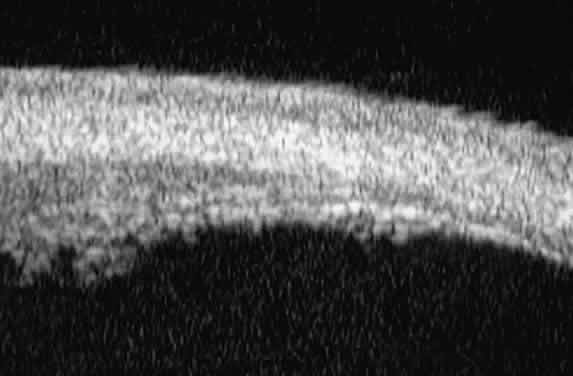

Radial, cross-sectional slices through the posterior ciliary body (Fig. 5) show the sclera as a highly reflective structure that can be easily differentiated from the underlying uveal and neuroepithelial layers of the pars plana. In most patients, UBM is not able to image the ora serrata, peripheral choroid, and peripheral retina.

Fig. 5. Radial UBM slice through pars plana of normal eye.

Additional slices through regions of interest can be obtained to evaluate specific features. For example, slices can be made through the pars plicata with the scanning plane concentric to the corneoscleral limbus (i.e., perpendicular to the previously made radial slices) (Fig. 6). Such images show the ciliary processes as a series of fingerlike projections.

Fig. 6. Transverse UBM slice through pars plicata of normal eye.